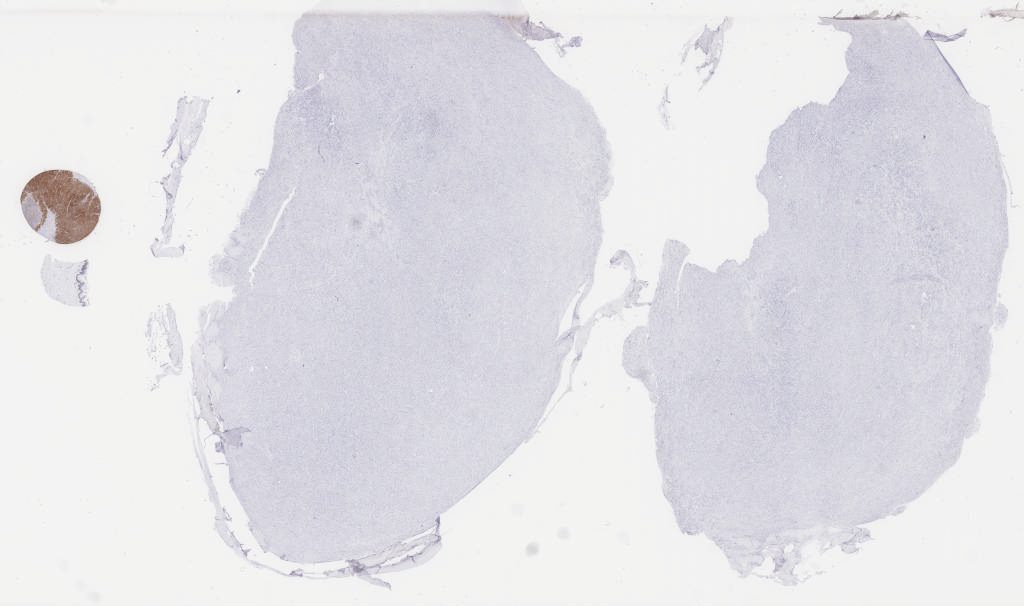

ema.svs

169319

x

96596

@

40X